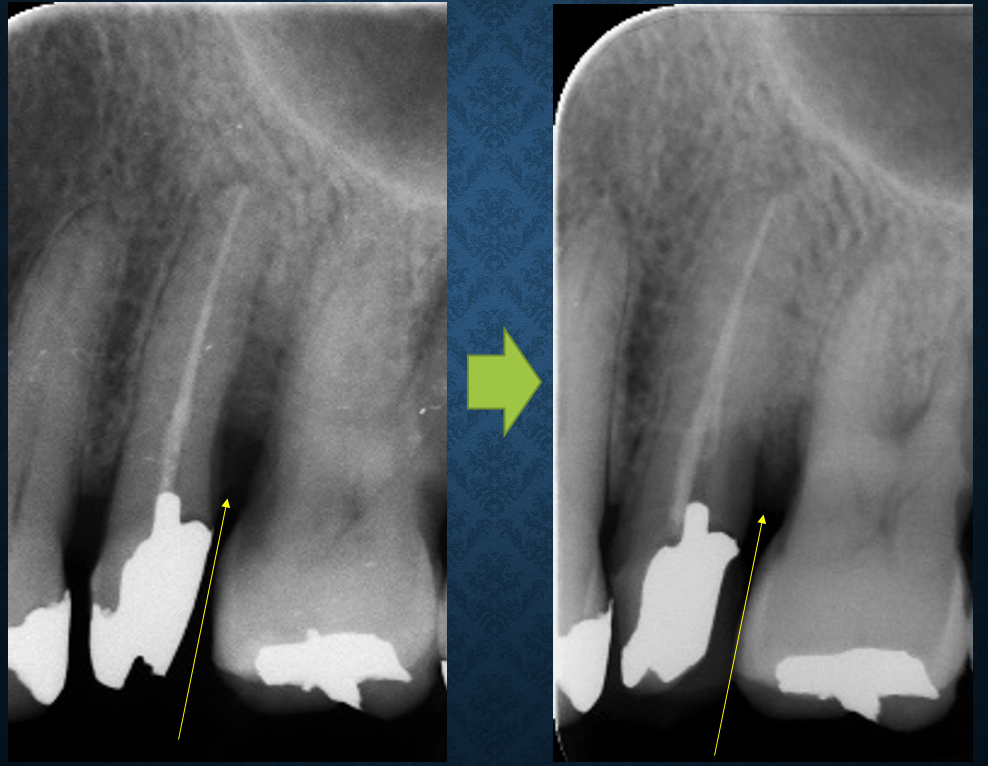

約1年前に歯周組織再生療法を行った患者さんがメンテナンスで来院されました。歯周組織のある程度の回復が確認され、歯周ポケットも浅くなり改善が認められました(写真をクリックして拡大してご覧ください)。比較的やりやすい単根歯であったことと患者さんのメンテナンス協力度がカギだったと思います。来月には福岡で水上哲也先生の歯周治療の考え方の変革と銘打って実習付きのセミナーに参加予定です。手技上の改良を加えて、より効率的なオペを目指したいと思います。